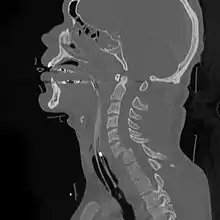

| A fracture of the base of the dens (a part of C2) as seen on CT. | |